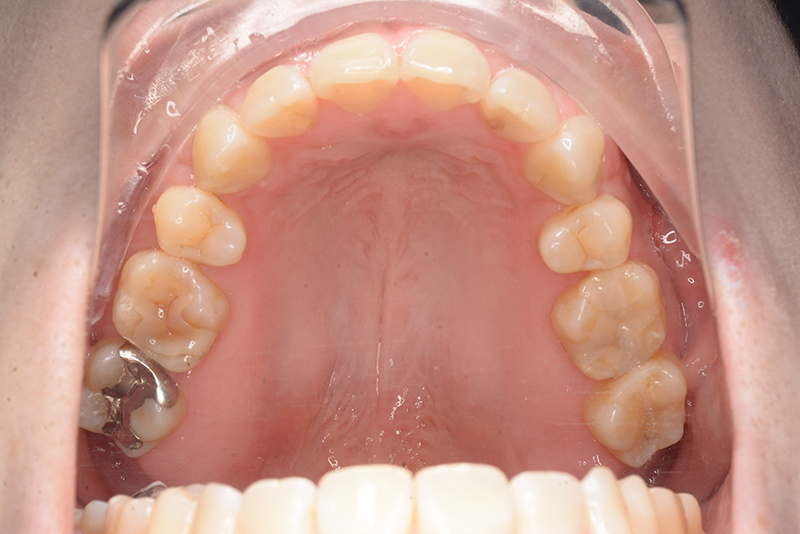

| 口腔内所見 | 臼歯関係はⅠ級、over jet 4.5mm、over bite -3.0mm。上下顎切歯部に軽度の叢生が認められ唇側傾斜をしつつ開咬を呈していた。 |

| 批評・予后 | 治療後において下顎角の開大も認められず歯軸の整直、咬合の緊密化が得られた。また上下顎前歯の後退と共に口元の突出感と口唇閉鎖不全の改善が認められた。 |